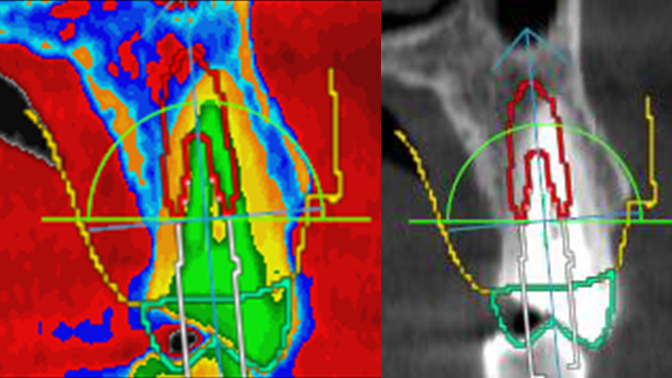

Clinical case: Digital Data Save concept in upper jaw premolar area

- Courtesy of Dr. Lysov Alexander Dmitrievich & Dr. Sofronov Matvey Vitalievich, Russia -

Keywords

AnyRidge, R2GATE, R2GATE guide, ISQ value, initial stability, immediate loading, KnifeThread, maxillary posterior, #14, Digital, Dr. Lysov Alexander Dmitrievich, Dr. Sofronov Matvey Vitalievich, zirconia abutment, CAD/CAM crown

“AnyRidge & R2GATE show stable results

after immediate extraction, immediate implant placement, & immediate loading,

even with low bone density.”